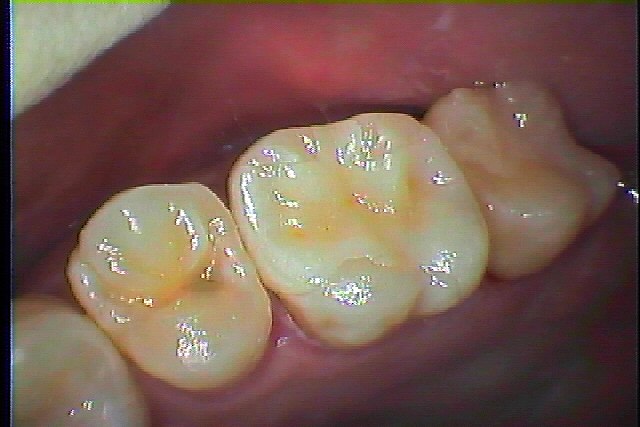

左上6番がこれも昨夜から痛み出してきて痛み止め飲んでも効かないとのこと|お知らせ |広島市安佐南区の歯科医院 左上6番がこれも昨夜から痛み出してきて痛み止め飲んでも効かないとのこと トップ お知らせ・ブログ お知らせ 左上6番がこれも昨夜から痛み出してきて痛み止め飲んでも効かないとのこと 左上6番がこれも昨夜から痛み出してきて痛み止め飲んでも効かないとのこと 遠心部に大きく穴が存在しています 虫歯が大きく神経まで達していました 根管治療をさせていただきました 痛みが取れました 根充後のデンタルになります CR樹脂にて土台を立てて型取りを行っています セレックセラミックにて修復しています Web診療予約 初めての方へ 選ばれ続ける理由 院内設備について 歯が痛いしみる一般歯科 歯がぐらぐらする歯周病 健康な歯を保ちたい予防歯科 子供の虫歯予防をしたい小児歯科 銀歯をセラミックに審美歯科 白い歯を目指しませんか?ホワイトニング 矯正専門医がいるので安心矯正歯科 抜けた歯を補いたいインプラント・入れ歯 医院案内 スタッフ紹介 メリィハウス歯科クリニックオフィシャルホームページ ラベンダー歯科クリニックオフィシャルホームページ お知らせ・ブログ ホーム 診療科目 一般歯科 歯周病治療 予防治療 小児歯科 審美治療 ホワイトニング 矯正歯科 入れ歯・インプラント マウスピース矯正 初めての方へ 院長・スタッフ 設備紹介 医院案内・アクセス メニューを閉じる